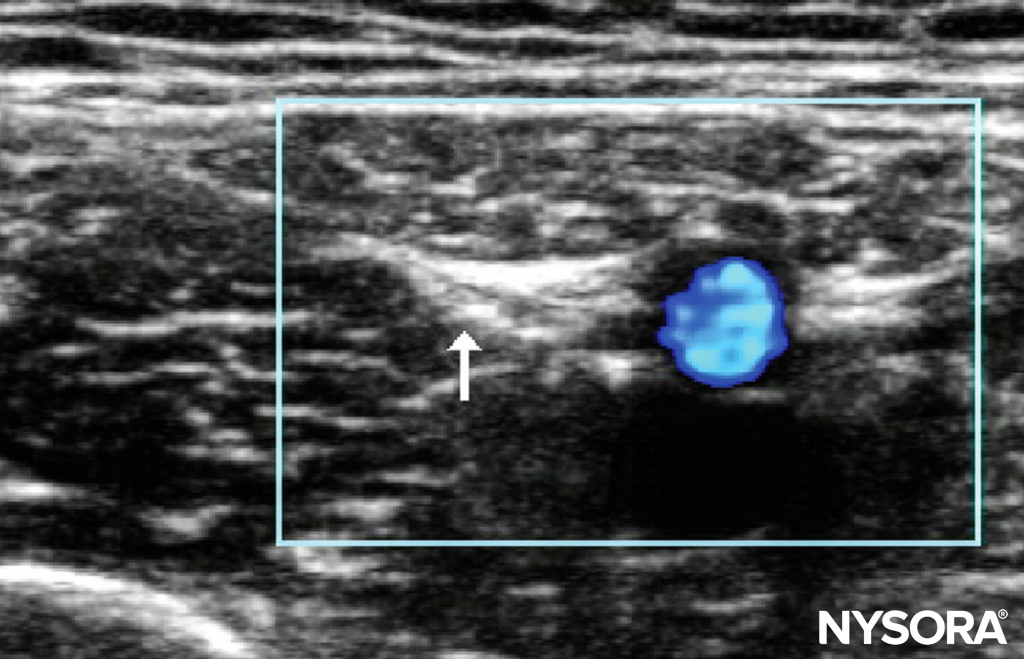

Ultrasound-Guided Technique A reliable location to identify the nerve is 10–20 mm below the anterior superior iliac spine, in the groove between the sartorius muscle and the tensor fascia lata. The lateral femoral cutaneous nerve is a small hyperechoic nerve (Figure 5). Note that the nerve may pass through the ligament or laterally to the anterior superior iliac spine.

FIGURE 5. Lateral cutaneous nerve of the thigh in a 6-year-old: probe position and relevant sonoanatomy.